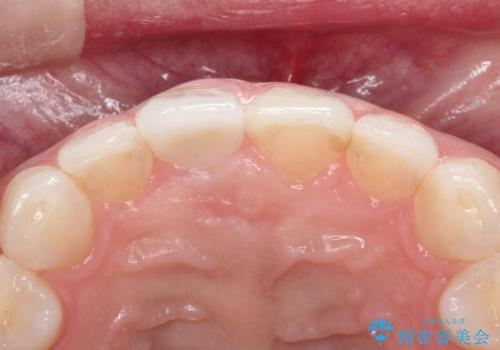

10年前に根管治療を他院で行っており、根尖性歯周炎の予防のため根管治療から行いました。被せものはオールセラミッククラウンで治療を行いました。

ホワイトニングもご希望されたのでホームホワイトニングも行いました。

治療について

10年前にラバーダムシート無しに根管治療を行っており、現在、症状は出ていませんが、根尖性歯周炎の予防のため根管治療から行いました。ホームホワイトニングを2週間行って頂き、その後、オールセラミッククラウンで治療を行っています。

※被せものでは歯と被せものの適合がとても大切になります。適合が悪い被せもの(歯と被せものの間に隙間がある)を入れるとそこに汚れが溜り虫歯の原因となります。当院では精度が高い被せものを追求するため、サージテル(拡大鏡)や型取りの材料にシリコン材を使用しています。